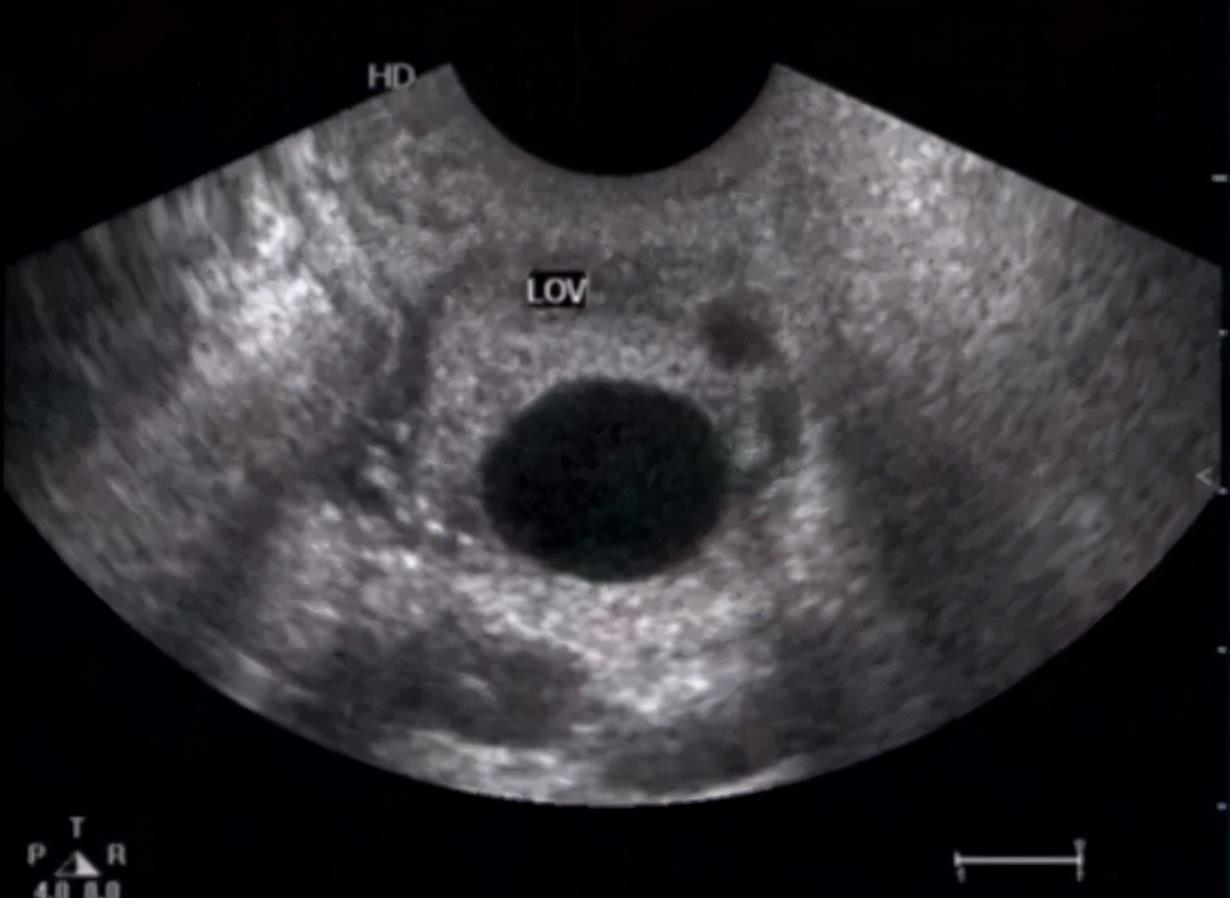

卵巢子宫内膜异位囊肿特点: 囊肿可在双侧卵巢或单侧卵巢发病,因病程的长短及月经周期时相不同,表现不同,可伴有痛经、也有不痛经,体检的时候才被发现的,早期超声表现与黄体血肿类似,典型的成熟巧囊表现为囊肿内细密均匀的光点状回声。需要动态复查,酌情手术治疗及辅助治疗;个别巧囊经过长时间的演进,也有变成癌的,所以也要引起重视!